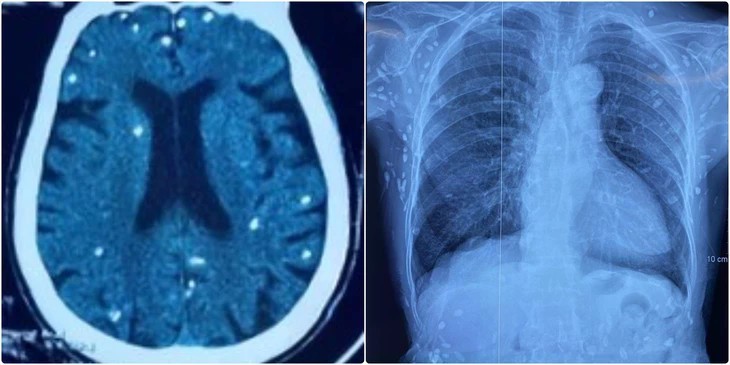

Hình ảnh chụp cắt lớp vi tính sọ não và X-quang ngực của bệnh nhân có nhiều tổn thương do nang sán - (Ảnh: BVCC).

Người bệnh được chuyển lên từ tuyến dưới vì rối loạn ý thức, đe dọa suy hô hấp, hình ảnh cắt lớp vi tính sọ não và X-quang ngực cho thấy rất nhiều nốt cản quang trong nhu mô não và dưới da vùng ngực-bụng.

Theo bác sĩ Nguyễn Thị Vân Anh, khoa hồi sức truyền nhiễm, Bệnh viện Trung ương Quân đội 108, mặc dù xét nghiệm kháng thể IgM với sán dây lợn âm tính, các tổn thương trên X-quang gợi ý người bệnh trước đây bị nhiễm ấu trùng sán dây lợn, sau đó các nang sán trở nên vôi hóa và tồn tại lâu dài trong cơ thể.

Nang sán dây lợn có thể tự thoái hóa hoặc bị vôi hóa, tạo nên nhiều hình ảnh cản quang phát hiện được trên phim X-quang như trường hợp bệnh nhân trên.